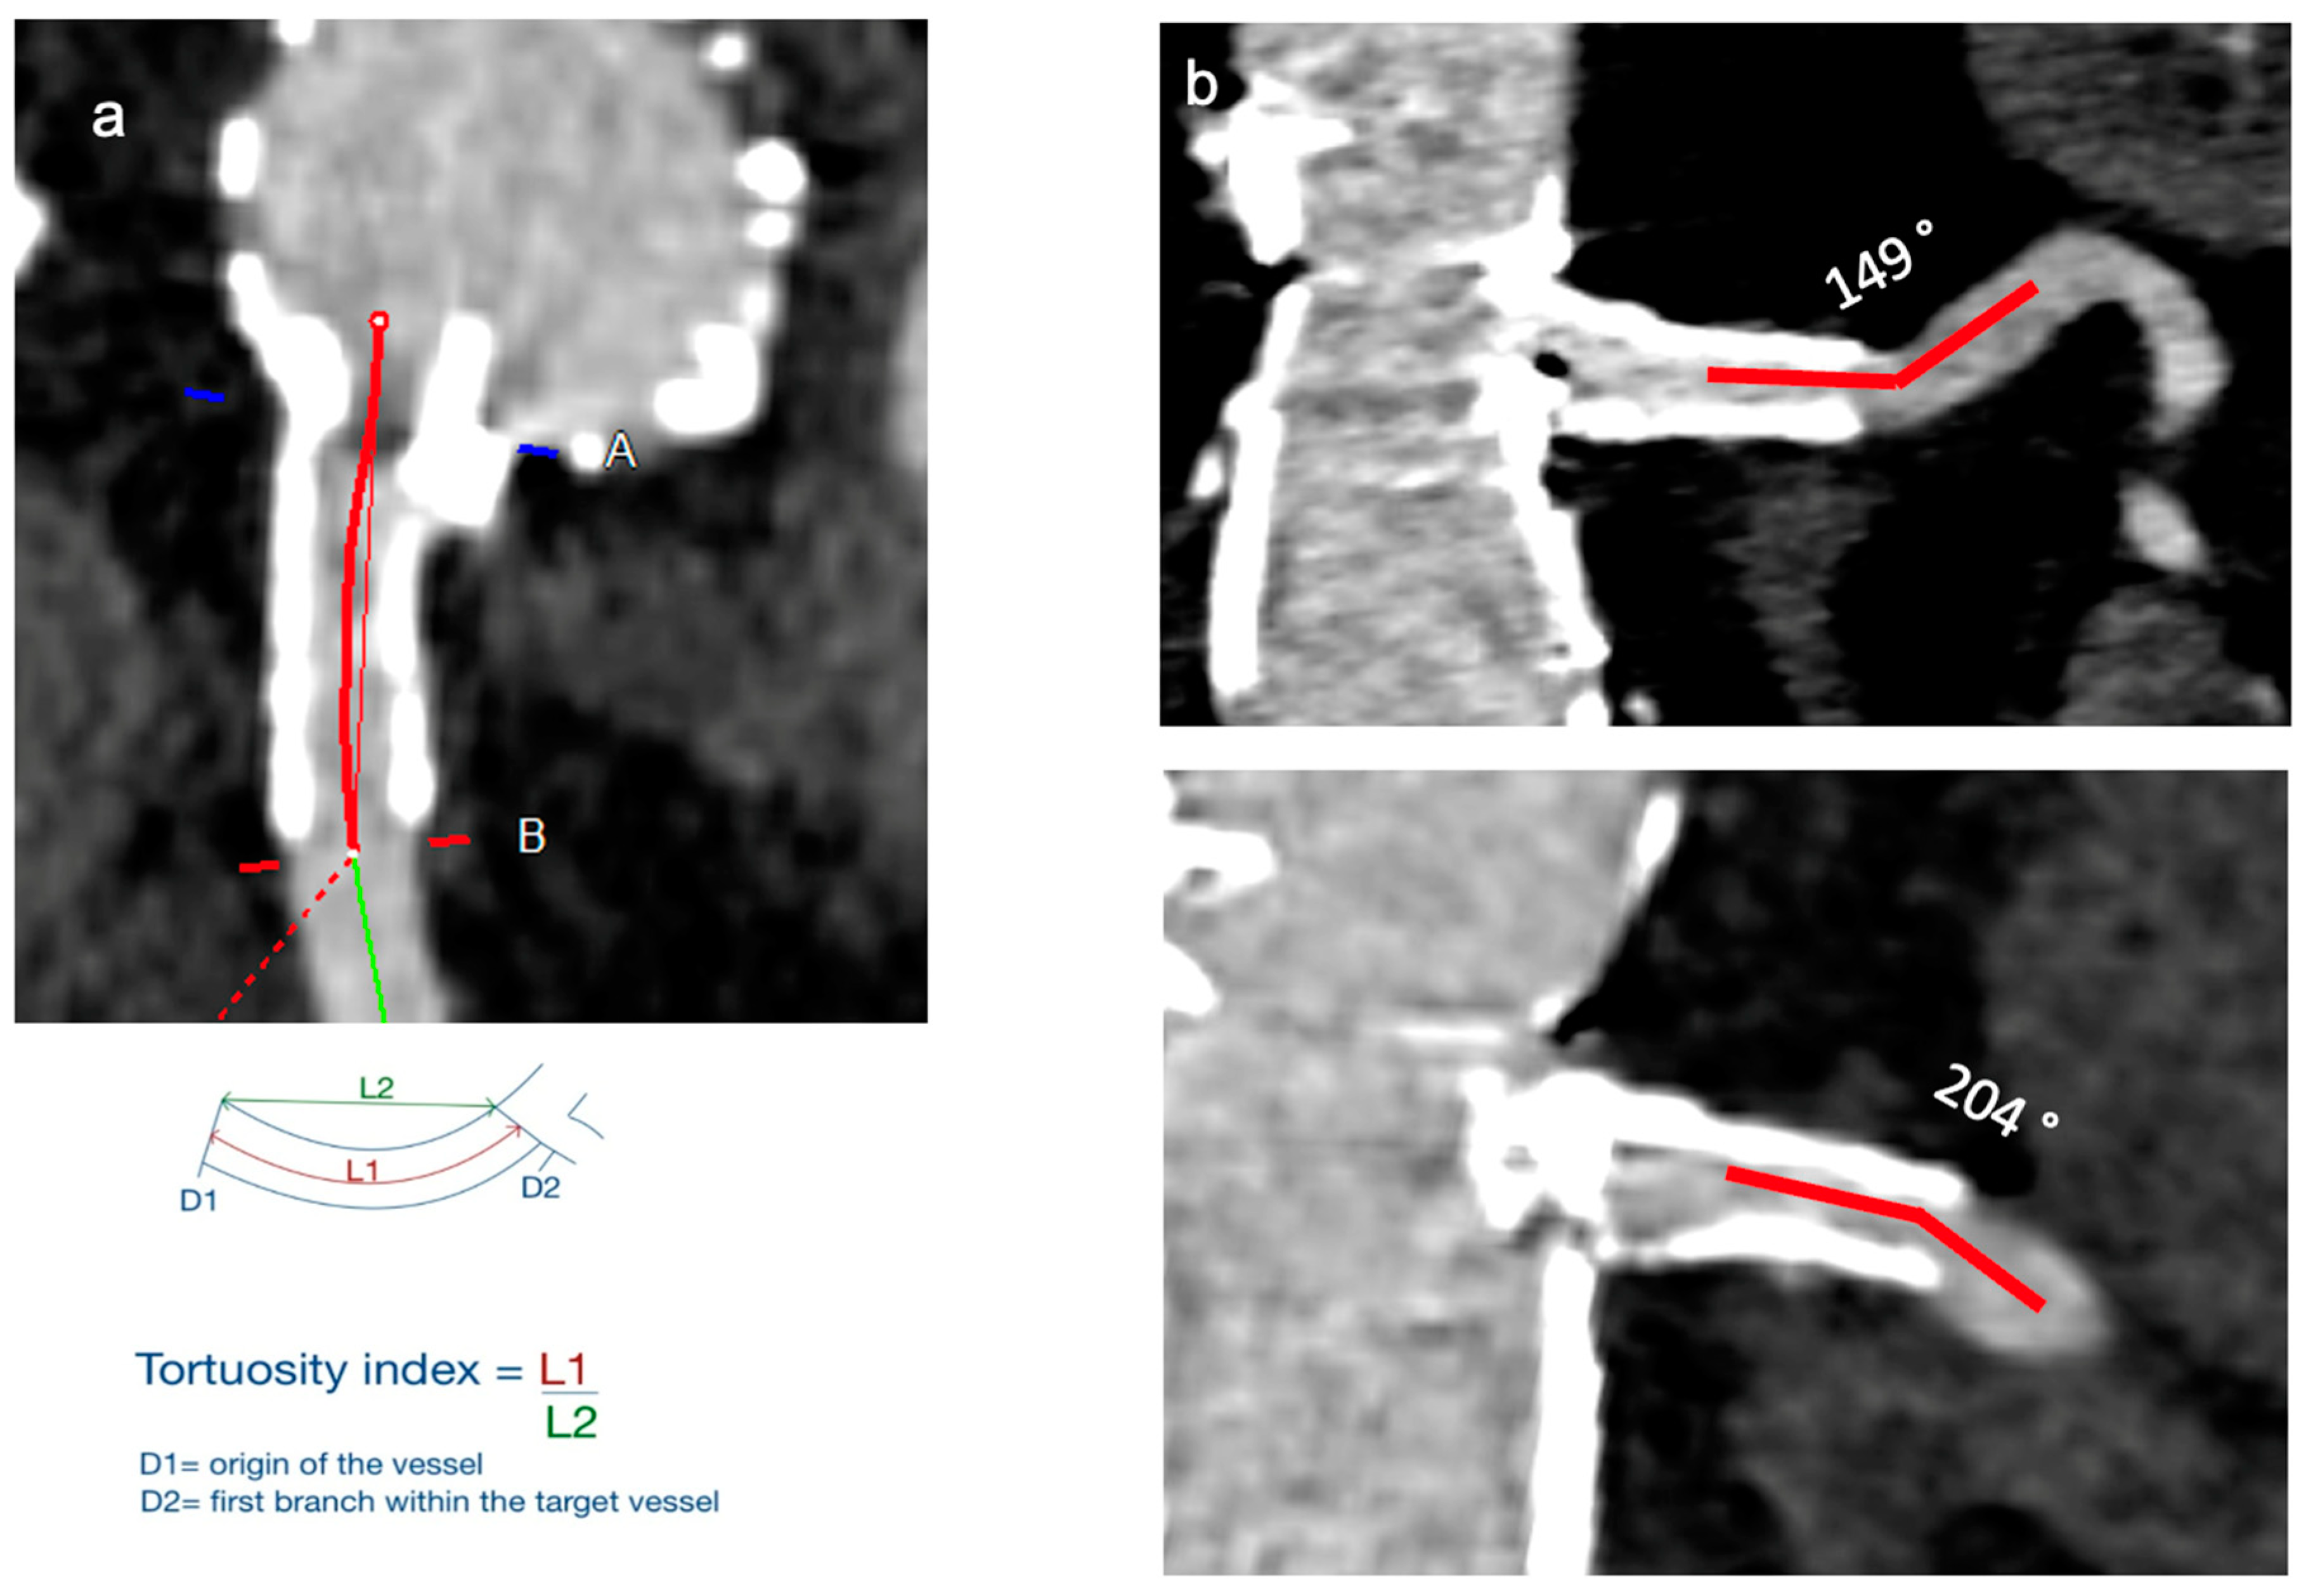

- Angle: measured as the angle between the target vessel and the aortic wall (Figure 1).

- Tortuosity index: calculated as a ratio between the length along the centerline and the linear distance between the orifice of the target vessel to 3 cm distal into the vessel (Figure 1).